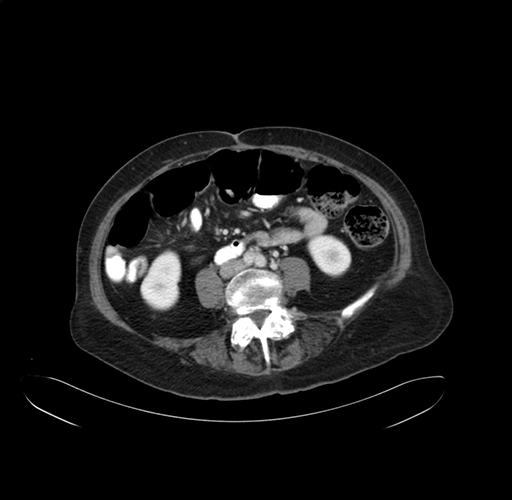

Pre-Chemo: Axial Venous

Axial Venous